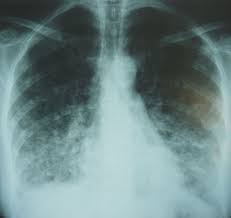

Los hallazgos de la radiología de tórax muestran típicamente un patrón intersticial bilateral, con predominio en bases y/o región perihiliar, aunque no es raro el patrón alveolar, pudiendo objetivarse en fases tempranas un componente nodular/ micronodular (2-10 mm) que puede llegar a presentar calcificaciones. Hay estudios 5 que recomiendan realizar una radiografía de tórax en todo paciente con varicela, independientemente de la presencia o no de clínica respiratoria, ya que la radiología de tórax presentó hallazgos aun no existiendo clínica respiratoria en el 33,3% de los pacientes.

Imagen 2. Radiografía de una neumonía por varicela